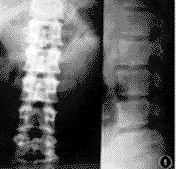

本组7例,4例症状完全消失,1例残留趾端、足背麻木,2例有轻微腰部酸痛感,手术结果均为优良。随访时间12~36个月,X线片示置入假体无一例松动、移位、脱出,无一例复发(图1,2)。

图2 术后腰椎正、侧位X线片,单枚TFC与矢状面呈45°置入,位置良好,L4-5 椎间隙增大